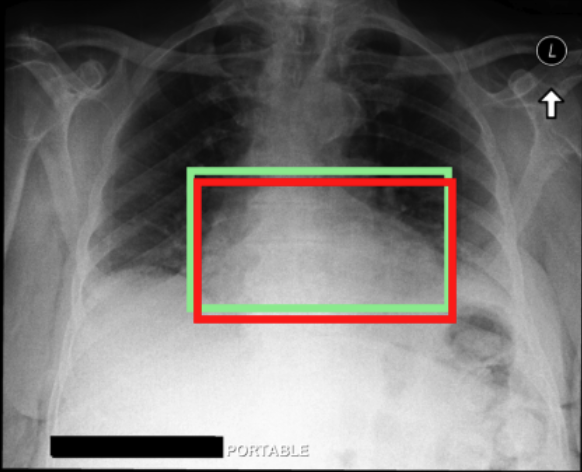

4.3.3 Visual grounding

In this section, we evaluate RadVLM’s visual grounding capabilities, which could help clinicians localize specific regions or pathologies on a CXR. This is particularly useful once a pathology has already been identified – either by a radiologist’s input or through our previously described AI tasks – since it allows one to pinpoint exactly where the abnormality appears on the image.

We report performance metrics for the three main grounding tasks RadVLM was trained on: anatomical grounding using the Chest Imagenome test set, abnormality grounding using the VinDr-CXR test set, and phrase grounding using the MS-CXR test set (Table 1). For each task, we use mean Average Precision (mAP) as our primary evaluation metric.

As mentioned in Table 2, some of the CXR-specific VLMs already have grounding capabilities. CheXagent was trained to handle both abnormality and phrase grounding tasks, while MAIRA-2 – originally trained to produce radiology reports with grounded observations – is also capable of predicting bounding box coordinates when provided with input text. After retrieving each model’s instruction template for generating bounding box coordinates (Appendix 1-Table 2), we evaluated both CheXagent and MAIRA-2 on all three grounding tasks performed by RadVLM.

Our results show that RadVLM performs well at localizing anatomical regions (e.g., “right lung”, “aortic arch”, illustrated in Figure 5a), achieving a mAP of 85.8 %, by far surpassing the other CXR grounding models (Table 4). This advantage is partly explained by including the Chest Imagenome dataset (and thus the anatomical grounding task) in the training set, which CheXagent and MAIRA-2 did not leverage. However, it remains a key feature for any grounding model to possess a fine-grained understanding of CXR anatomy.

For the abnormality grounding task, RadVLM is less consistent (Figure 5b), likely due to higher sparsity of abnormality locations and labels, yet it still achieves best performance (Table 4). For the phrase grounding task, while MAIRA-2 and CheXagent demonstrate great performance, RadVLM surpasses them with a mAP of 81.8% (Table 4), presumably benefiting from the newly released PadChest-GR dataset (Castro et al.,, 2024) used for training.

Overall, these results show that our instruction tuning strategy for visual grounding (covering three essential tasks), combined to a modern VLM backbone, offers a promising avenue to help clinicians localize anatomical and pathological features during a CXR exam. Furthermore, providing fine-grained details within an LLM-generated output may also enhance the ability to answer grounded questions in a multi-turn setting, as we explore next.

a. Anatomical grounding

silhouette

junction

structures

lung

abdomen

mediastinum

arch

b. Abnormality grounding

thickening

fibrosis

enlargement

lung disease

| Anatomical grounding | Abnormality grounding | Phrase grounding | |

| CheXagent | 6.2 | 26.0 | 69.7 |

| MAIRA-2 | 19.8 | 11.3 | 80.1 |

| RadVLM | 85.8 | 34.6 | 81.8 |